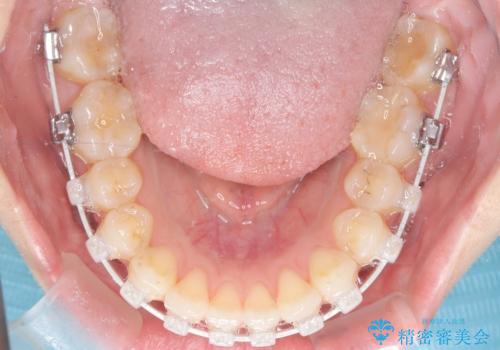

- 右上の八重歯と歯並びのデコボコを気にされて来院されました。精密な検査の結果、歯列のスペースがわずかに不足していることが判明。患者様の「抜歯を避けたい」というご希望を最大限に尊重し、アンカースクリュー(TAD)を用いて奥歯(臼歯部)全体を後方へ移動させることで、八重歯が並ぶスペースを確保する治療計画を立案しました。装置にはワイヤー矯正を使用し、確実で効率的な歯の移動を目指します。

今回のワイヤー矯正治療では、抜歯せずに歯を並べるスペースを作るため、特殊な小さなインプラントであるアンカースクリュー(TAD)を一時的に使用しました。このアンカースクリューを固定源として、奥歯(臼歯部)全体を後方へ遠心移動させました。従来の矯正では難しかったこの奥歯の移動を確実に行うことで、前歯の八重歯を適切な位置に並べるスペースを確保。治療の結果、抜歯することなく右上の八重歯と叢生が解消され、機能的にも審美的にも整った美しい歯並びを獲得していただけました。